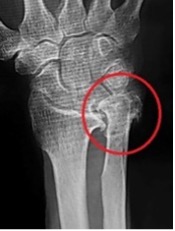

橈骨遠位端骨折に対する鏡視併用手術

橈骨遠位端骨折は頻度の高い骨折の一つで、特に関節内骨折については関節鏡を併用し従来のX線のみでは整復が不十分な関節面の整復を行っています。

術前

術後